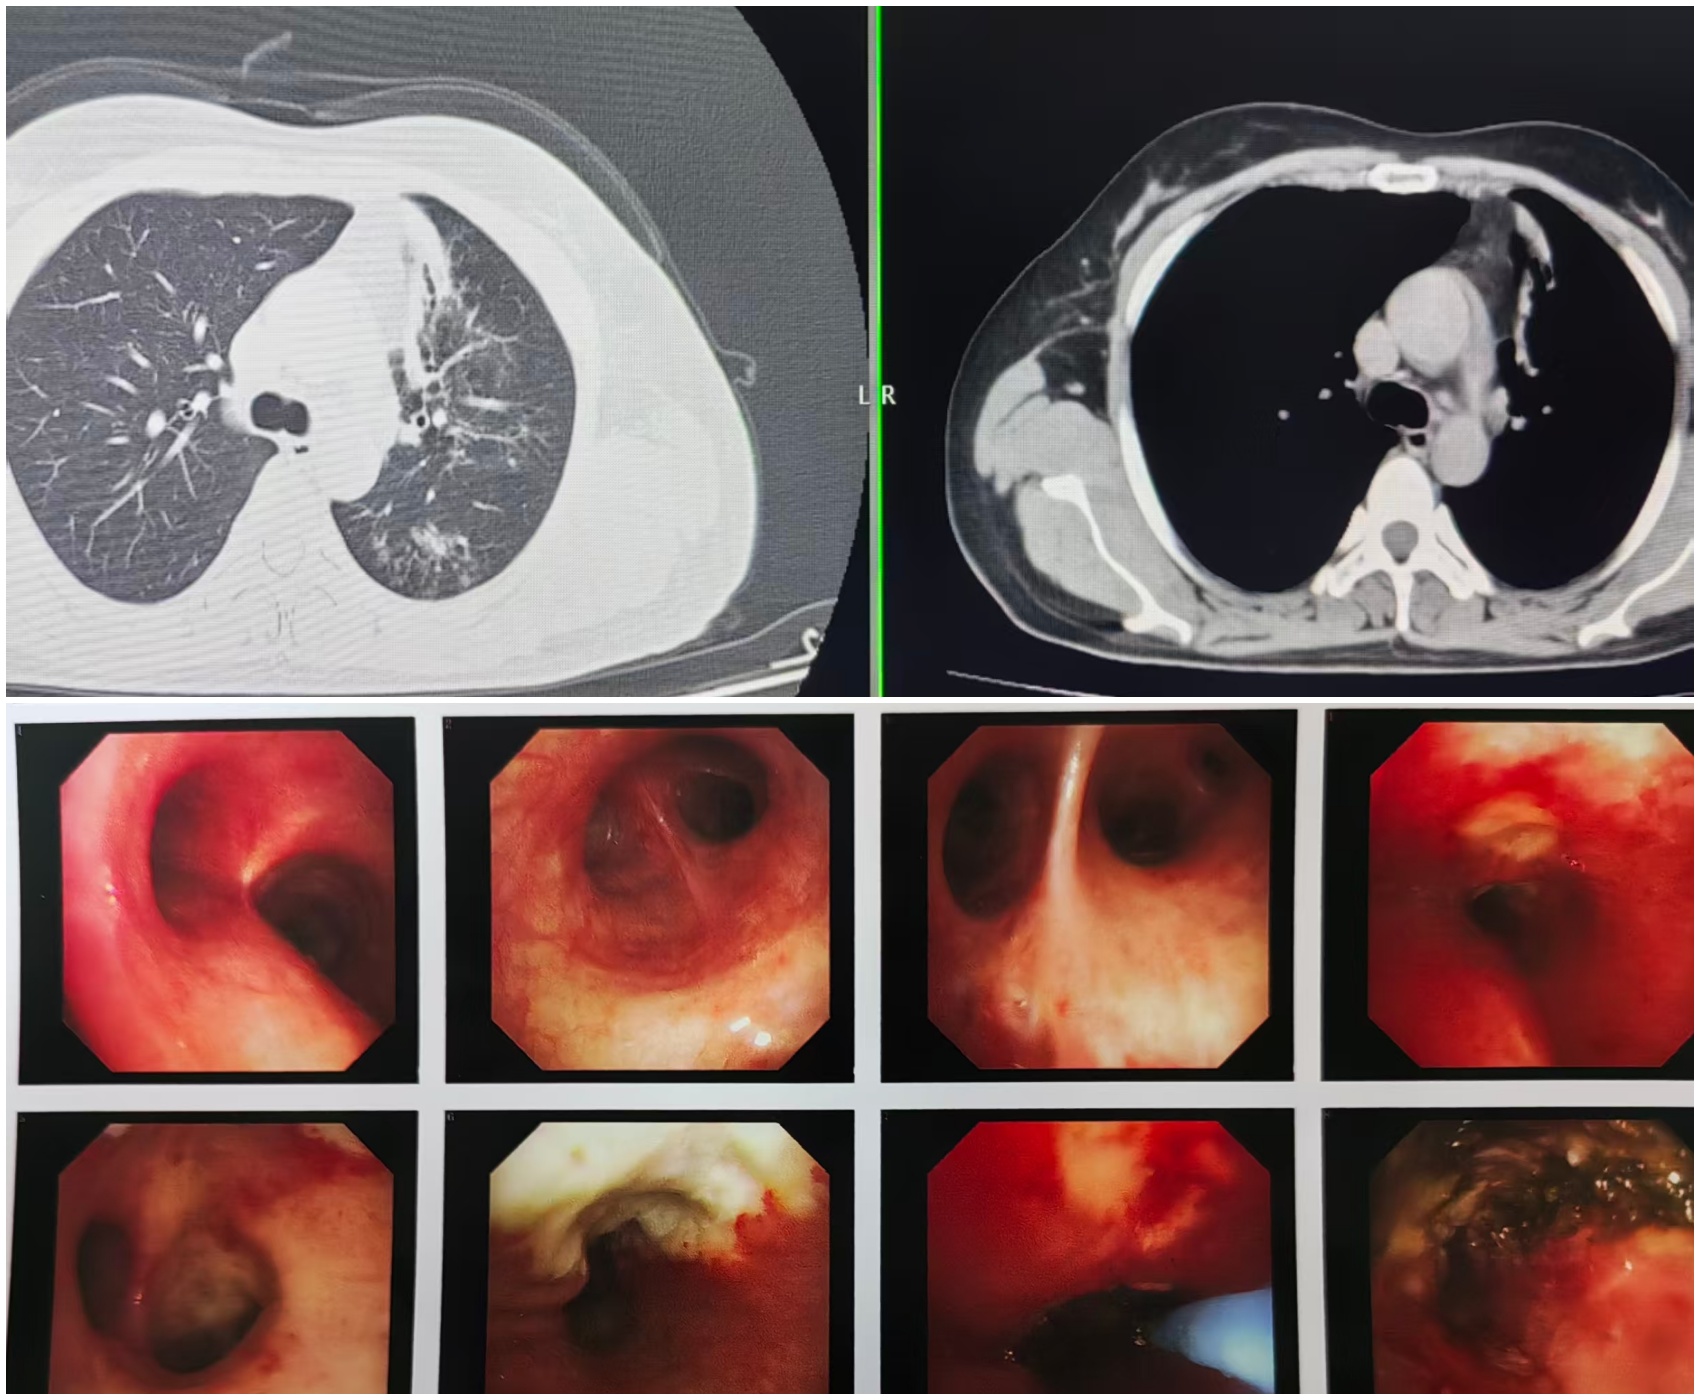

患者王女士(化名)的“呼吸之路”布滿坎坷。她曾確診肺結(jié)核,因未接受規(guī)范治療,病情遷延不愈。近一年來(lái),反復(fù)咳嗽成為她的 “心頭患”,尤其在接觸煙味后,咳嗽癥狀會(huì)即刻加重。半月前,王女士咳嗽、咳痰癥狀突然加劇,還伴隨胸痛不適,遂緊急前往我院就診。檢查結(jié)果令人揪心:胸部 CT 提示左肺多發(fā)性病變,進(jìn)一步的氣管鏡檢查顯示,其左肺上葉支氣管已被大量干酪樣壞死物完全堵塞,肺葉面臨完全坍塌的危機(jī),若不及時(shí)干預(yù),肺功能將遭受永久性損傷。?

手術(shù)當(dāng)日,在麻醉與圍術(shù)期醫(yī)學(xué)科團(tuán)隊(duì)的緊密配合下,呼吸內(nèi)鏡團(tuán)隊(duì)精準(zhǔn)操作,將支氣管鏡順利送達(dá)病灶部位。醫(yī)生利用氬氣刀技術(shù),對(duì)堵塞氣道的干酪樣壞死物進(jìn)行逐層、精準(zhǔn)消融,成功打通堵塞的支氣管管腔。整個(gè)手術(shù)過(guò)程行云流水,出血量極少,患者生命體征平穩(wěn),術(shù)后安返病房,目前恢復(fù)狀況良好。